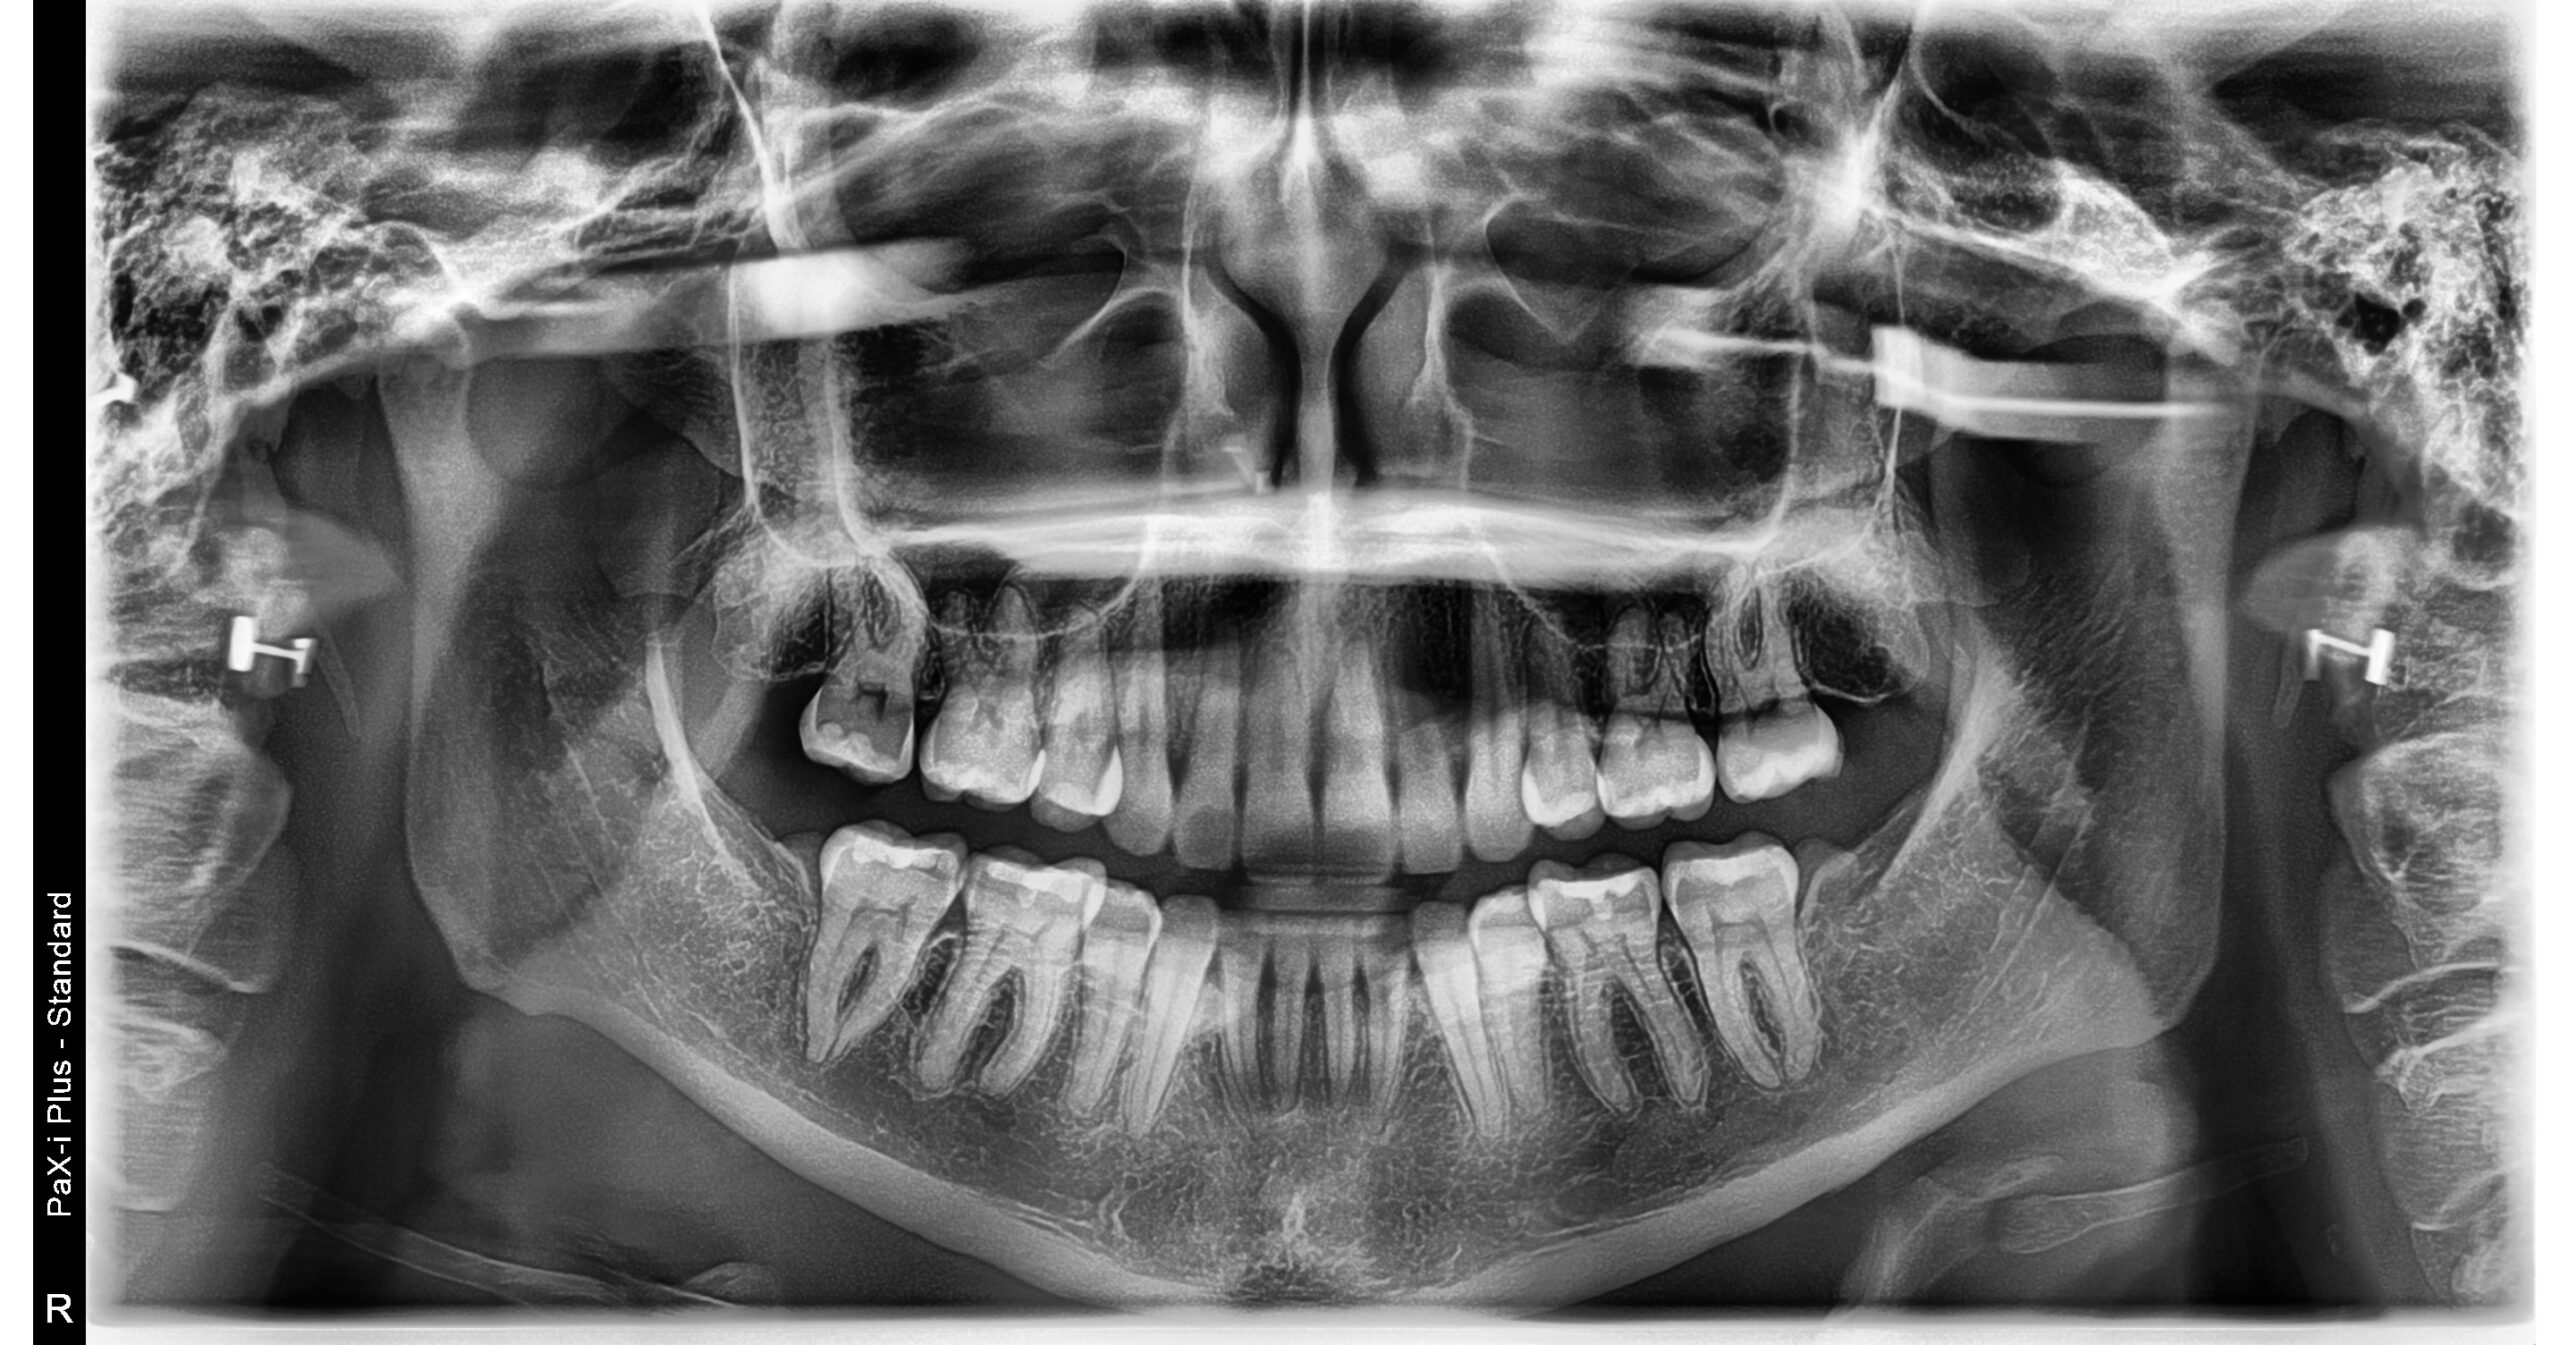

A 34- year old Caucasian female presents with a chief concern of “I don’t like my overbite and spaces between my front teeth.”